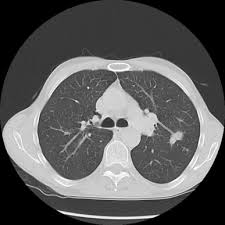

Can Lung Cancer Be Mistaken For Tuberculosis / Possible Causes Of A Lung Mass - Often, people with recurrent bouts of pneumonia tend to have unidentified lung cancer that can progress to advanced stages without appropriate treatment.. Tuberculosis is a chronic infective disease mainly caused by mycobacterium tuberculosis. In comparison, those diagnosed with tuberculosis prior to lung cancer (n = 11) had more. Various viruses, bacteria, and fungi can cause pneumonia. Pulmonary tb may exhibit a variety of radiological features and may imitate other lung diseases, including cancer. Therefore it's often difficult to know when it's cancer, and some doctors are too quick to diagnose it out of fear.

Pulmonary Tuberculosis Role Of Radiology In Diagnosis And Management Radiographics from pubs.rsna.org When the fungus is just a nodule, you likely will not have symptoms. About 230,000 new cases of lung cancer are diagnosed annually, and about 160,000 lung cancer patients do not survive for more than five years. A condition called sarcoidosis, most commonly found in the lungs, can be mistaken for cancer, tuberculosis, or other infections, as its symptoms are similar. Smokers have the greatest risk of developing lung cancer, and quitting smoking greatly. Tuberculosis is a chronic infective disease mainly caused by mycobacterium tuberculosis. Pulmonary tb may exhibit a variety of radiological features and may imitate other lung diseases, including cancer. In patients with concurrent illness (n = 14), treatment for tuberculosis was successful except for one case. Now uncommon, lung abscesses usually result from a severe infection such as pneumonia or tuberculosis or from the aspiration of infectious material into the lungs from the mouth.

Differentiation according to the radiological findings can not be provided.

English International Union Against Tuberculosis And Lung Disease from img.yumpu.com Lung cancer cases could be mistaken for covid, charities warn this article is more than 7 months old similarity of symptoms and worries about seeking attention may delay diagnoses Tuberculosis, but other mycobacteria occasionally infect humans, like m. Tamura et al analyzed 25 cases with both lung cancer and pulmonary tuberculosis encountered at tokyo national chest hospital between 1991 and 1998. However, prospective data on tuberculosis and lung cancer risk are limited. For this reason, lung cancer may be misdiagnosed as conditions such as pneumonia, asthma, tuberculosis, or bronchitis. When the fungus is just a nodule, you likely will not have symptoms. Intracellulare causing the mycobacterium avium complex (mac) disease. Pulmonary tb may exhibit a variety of radiological features and may imitate other lung diseases, including cancer.

Usually monitor for tb in clinical trials—and it's possible the nodules that develop from the infection could be mistaken for additional cancer growths. Tuberculosis is a chronic infective disease mainly caused by mycobacterium tuberculosis. Smokers have the greatest risk of developing lung cancer, and quitting smoking greatly. Therefore it's often difficult to know when it's cancer, and some doctors are too quick to diagnose it out of fear. Tamura et al analyzed 25 cases with both lung cancer and pulmonary tuberculosis encountered at tokyo national chest hospital between 1991 and 1998. Often, people with recurrent bouts of pneumonia tend to have unidentified lung cancer that can progress to advanced stages without appropriate treatment. Intracellulare causing the mycobacterium avium complex (mac) disease. Find out if this is available in your part of the world. Lung cancer results in more fatalities in the united states than any other kind of cancer. Bacteremic patients and patients who aspirate can develop multiple lung abscesses. Differentiation according to the radiological findings can not be provided. Coexistence of mycobacterium xenopi with lung cancer has been reported. Lung cancer cases could be mistaken for covid, charities warn this article is more than 7 months old similarity of symptoms and worries about seeking attention may delay diagnoses